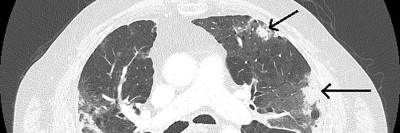

Bildnachweise

Kind erhält Leukämie Therapie/© FatCamera / Getty Images / iStock (Symbolbild mit Fotomodell), Immuncheckpointinhibitoren binden an Krebszelloberflächenproteine /© Juan Gärtner / stock.adobe.com, Arzt misst Blutzucker per Glucometer/© geargodz / Stock.adobe.com (Symbolbild mit Fotomodell), CT der Lunge mit Konsolidierungen (Pfeile) und Milchglastrübungen bei einer immunvermittelten Pneumonitis/© Minuth-Fuchs, K.L., Schulz, C. / all rights reserved Springer Medizin Verlag GmbH, Hepatozelluläres Karzinom im Lebersegment VIII/© Wengert, G. et al. / all rights reserved Springer Medizin Verlag GmbH, Blutabstrich der chonisch lymphatischen Leukämie/© jarun011 / Getty Images / iStock, Endobronchialer Befund mit exophytischem Tumor im Bereich des rechten Oberlappens/© Möller, M., Schütte, W. / all rights reserved Springer Medizin Verlag GmbH, Mann nimmt eine Tablette ein/© Jelena Stanojkovic / stock.adobe.com (Symbolbild mit Fotomodell), Thymom mit pleuraler Aussaat rechts im Masaoka-Koga-Stadium IVa./© Ried, M. et al. / all rights reserved Springer Medizin Verlag GmbH, Patientin schaut besorgt auf Infusionsbeutel/© KatarzynaBialasiewicz / Getty Images / iStock (Symbolbild mit Fotomodellen), Ältere Frau nimmt Tablette ein/© amenic181 / stock.adobe.com (Symbolbild mit Fotomodell), Generalisierte, konfluierende, kokardenartige Erytheme mit zentraler Blase/© Springer Medizin Verlag GmbH, Bronchialkarzinom/© Dr. Myriam Koch , Pulmonales Adenokarzinom bei Diagnosestellung/© Springer Medizin, Bestrahlung eines Lungenkarzinoms/© Springer Medizin Verlag GmbH, Search Icon, Ältere Frau fasst sich an die Brust/© Jelena Stanojkovic / Stock.adobe.com (Symbolbild mit Fotomodell), Person setzt DNS-Probe in Maschine ein/© Vit Kovalcik / stock.adobe.com, Mann raucht Joint/© Daniel Sierralta / Westend61 / stock.adobe.com (Symbolbild mit Fotomodell), Blut in Toilette/© stylefoto24 / stock.adobe.com